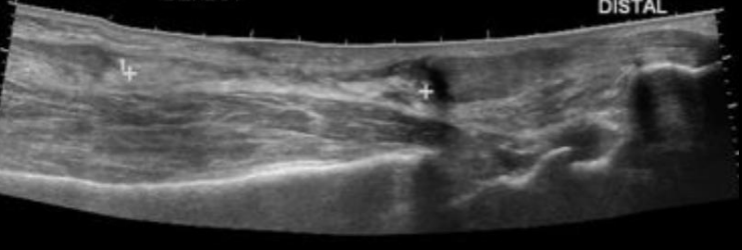

Q

Utilidad US

Limitada

Permite evaluar ATFL

Lesión ATFL